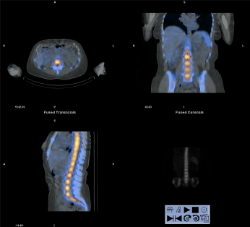

Molecular radiotherapy dosimetry

Optimal safe and effective use of molecular radiotherapy (MRT) techniques requires similar techniques to those utilised in external beam radiotherapy. We have developed pragmatic, patient-specific dosimetry solutions for a number of target and organs at risk. We use these techniques clinically and as part of multi-centre clinical trials evaluating the safety and efficacy of MRT.

The picture above shows an example of bone marrow uptake of labelled antibody (colour) superimposed on the grey scale CT image of anatomy. The very high uptake in marrow is used to treat patients with haematological malignancies such as leukaemia. All the bone marrow is ablated including the disease and the patient then undergoes a bone marrow transplant.